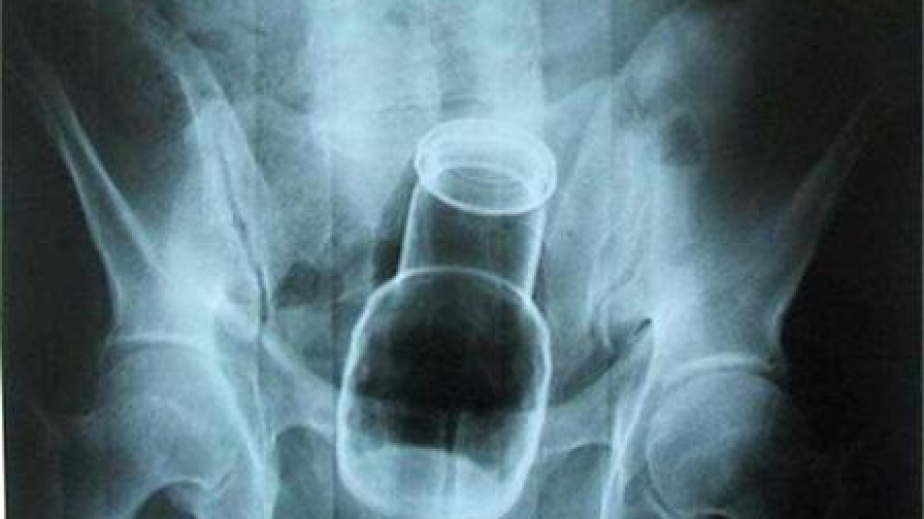

Търновски хирурзи извадиха флакон с пяна за бръснене от ректума на 35-годишенмъж.Пациентът, който е баща на 2 деца, обяснил, че изпуснал пяната, докато себръснел в банята. Навел се да вземе флакона, но се подхлъзнал и се нанизал нанего. Търновецът опитал сам да се справи с деликатната ситуация, но флаконът билпотънал дълбоко и се наложило да потърси лекарска помощ.Докторите успели да отстранят чуждото тяло по механичен път, без да се налагаоперация. Те проявили дискретност и не разкрили пред семейството съмненията си,че мъжът се е самозадоволявал.Наскоро в хирургията на търновската болница извадили струговано краче натабуретка от ануса на друг млад мъж."Пациентът обясни, че е бил седнал на края на табуретката, столчето сесчупило и крачето с дължина 15 см и диаметър 3-4 см влязло в ануса му. Тогаваситуацията бе по-опасна и се наложи операция", разказа д-р Николен Стойнов.Докато практикувал като лекар , сегашният зам.-кмет д-р Иво Найденов пъкспасил човек, който си пъхнал вибратор./24 часа